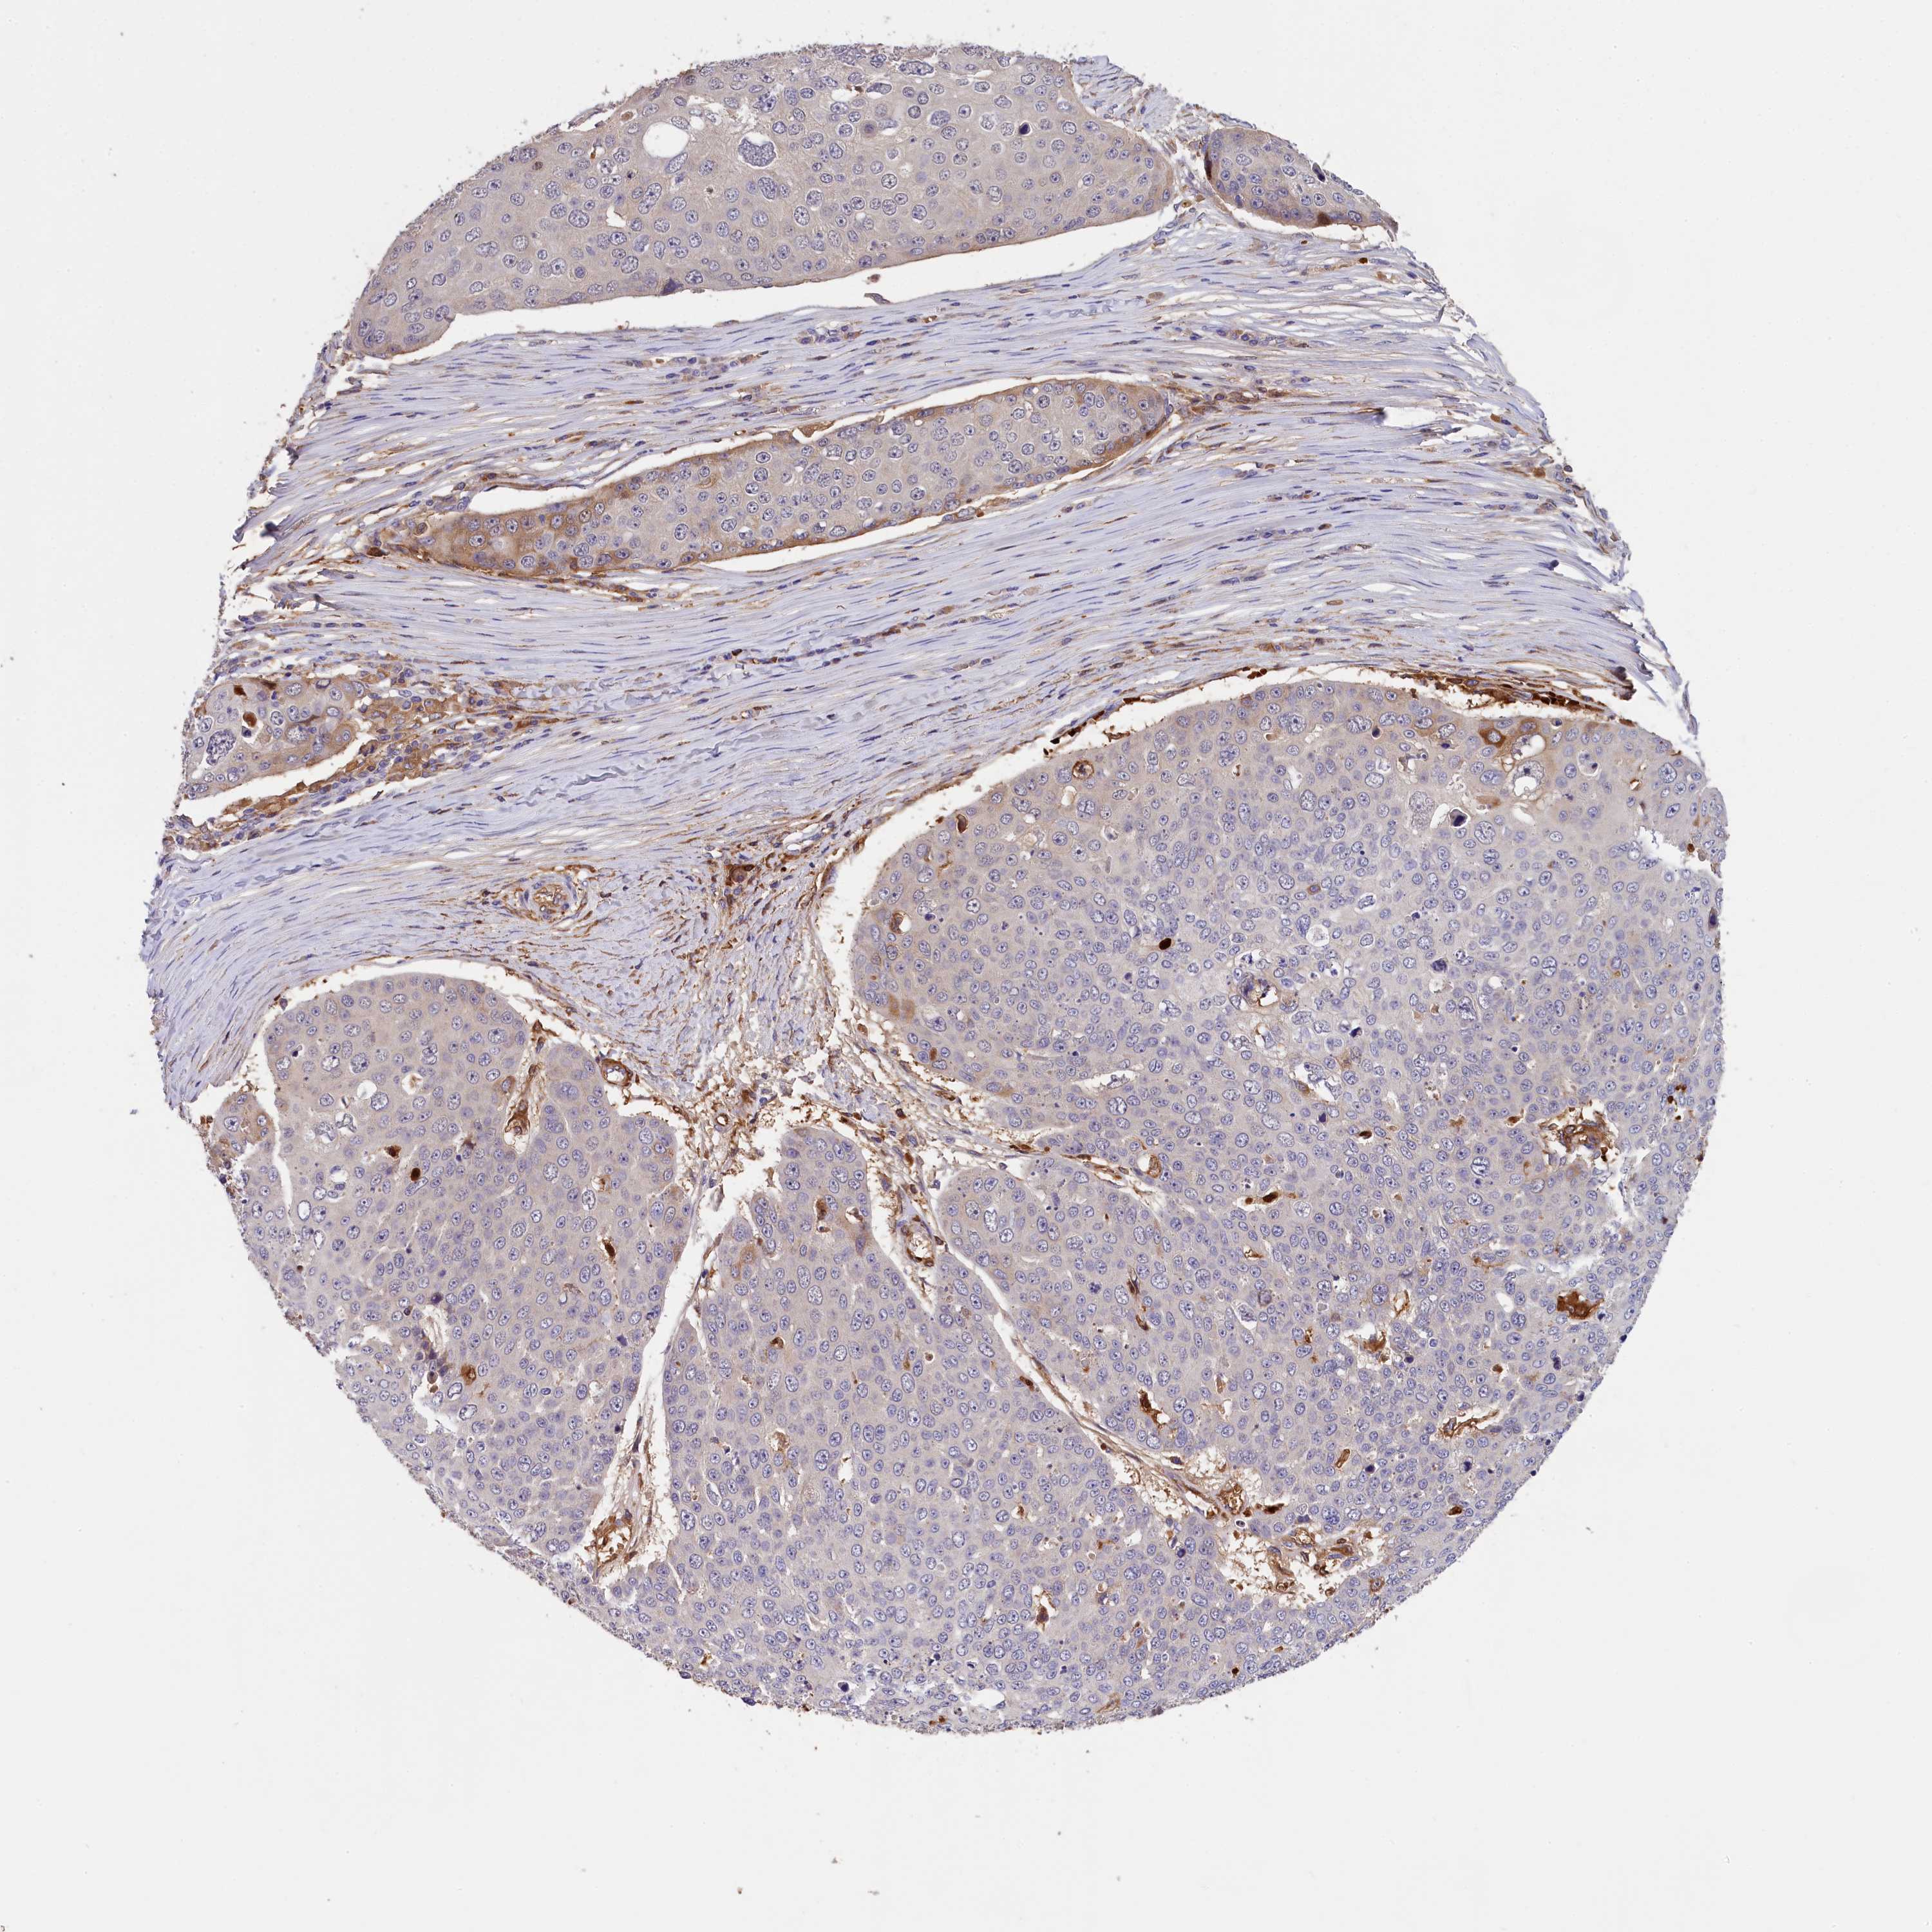

SKIN CANCER - Protein expressioni

A mouse-over function shows sample information and annotation data. Click on an image to view it in a full screen mode. Samples can be filtered based on level of antibody staining by selecting one or several of the following categories: high, medium, low and not detected. The assay and annotation is described here.

Antibody stainingi

Antibody staining in the annotated cell types in the current human tissue is reported as not detected, low, medium, or high, based on conventional immunohistochemistry profiling in selected tissues. This score is based on the combination of the staining intensity and fraction of stained cells.

Each image is clickable and will lead to virtual microscopy that enables deeper exploration of all samples and also displays staining intensity scores, fraction scores and subcellular localization as well as patient and tissue information for each sample.

Antibody HPA041131

Antibody HPA041214

Basal cell carcinoma

Squamous cell carcinoma, NOS